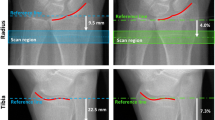

In HR-pQCT, a standard protocol recommended by the manufacturer is utilized for most studies [14, 82]. The patient’s forearm or ankle is immobilized in a carbon fiber cast fixed within the gantry of the scanner. A single scout projection image of the distal radius or tibia is acquired to define the tomographic scan region. This scout image is acquired at an AP orientation at the wrist and at an oblique (45°) anterolateral-posteromedial orientation at the ankle. This tomographic region spans 9.02 mm in length (110 slices) and is localized to a fixed offset proximal from either the radial or tibial midjoint line and extends proximally. The offset is 9.5 mm in the radius and 22.5 mm in the tibia (Fig. 4). This method does not account for differences in bone length and may be a confounding source of variability in cross-sectional studies [16]. In the radius, the default axial scan location partially includes the most common site for fracture and location, where the bone microstructure is most strongly correlated to experimental strength of the forearm under a simulated falling load [106].

Scout acquisition is used to define the HR-pQCT scan region for (A) the distal radius and (B) the distal tibia. The solid green region corresponds to the imaging location and consists of 110 slices spanning 9.02 mm longitudinally. In the radius the scan region is fixed 9.5 mm proximal from the midjoint line, while in the tibia the scan region is 22.5 mm proximal from the tibial plafond. HR-pQCT = high-resolution peripheral quantitative CT.